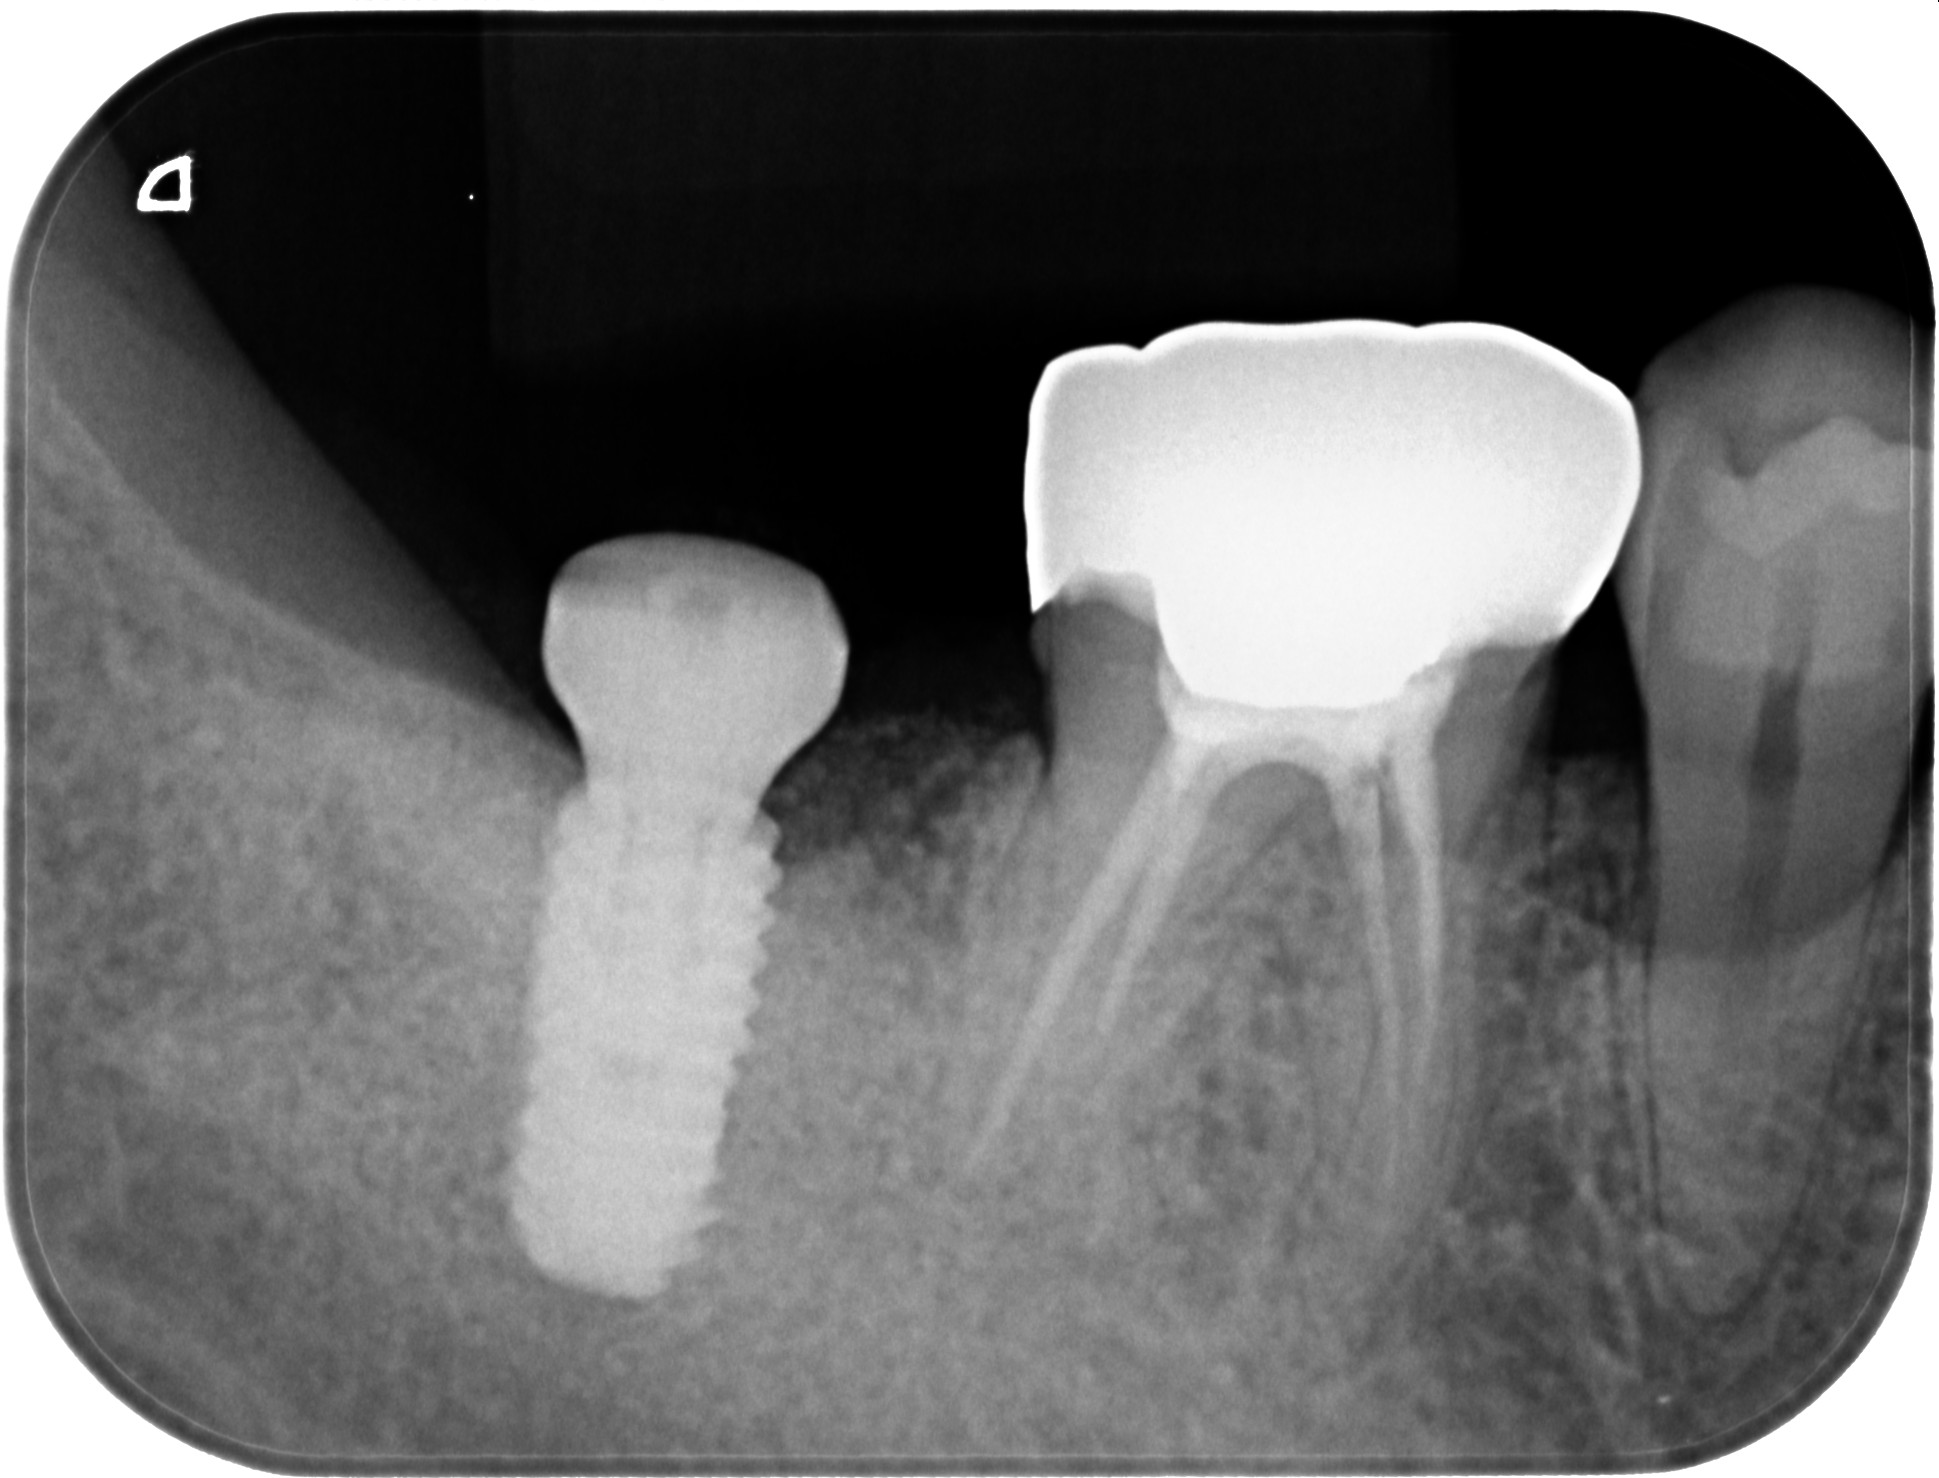

インプラント後、最終的な被せ物(ジルコニア)装着後のエックス線